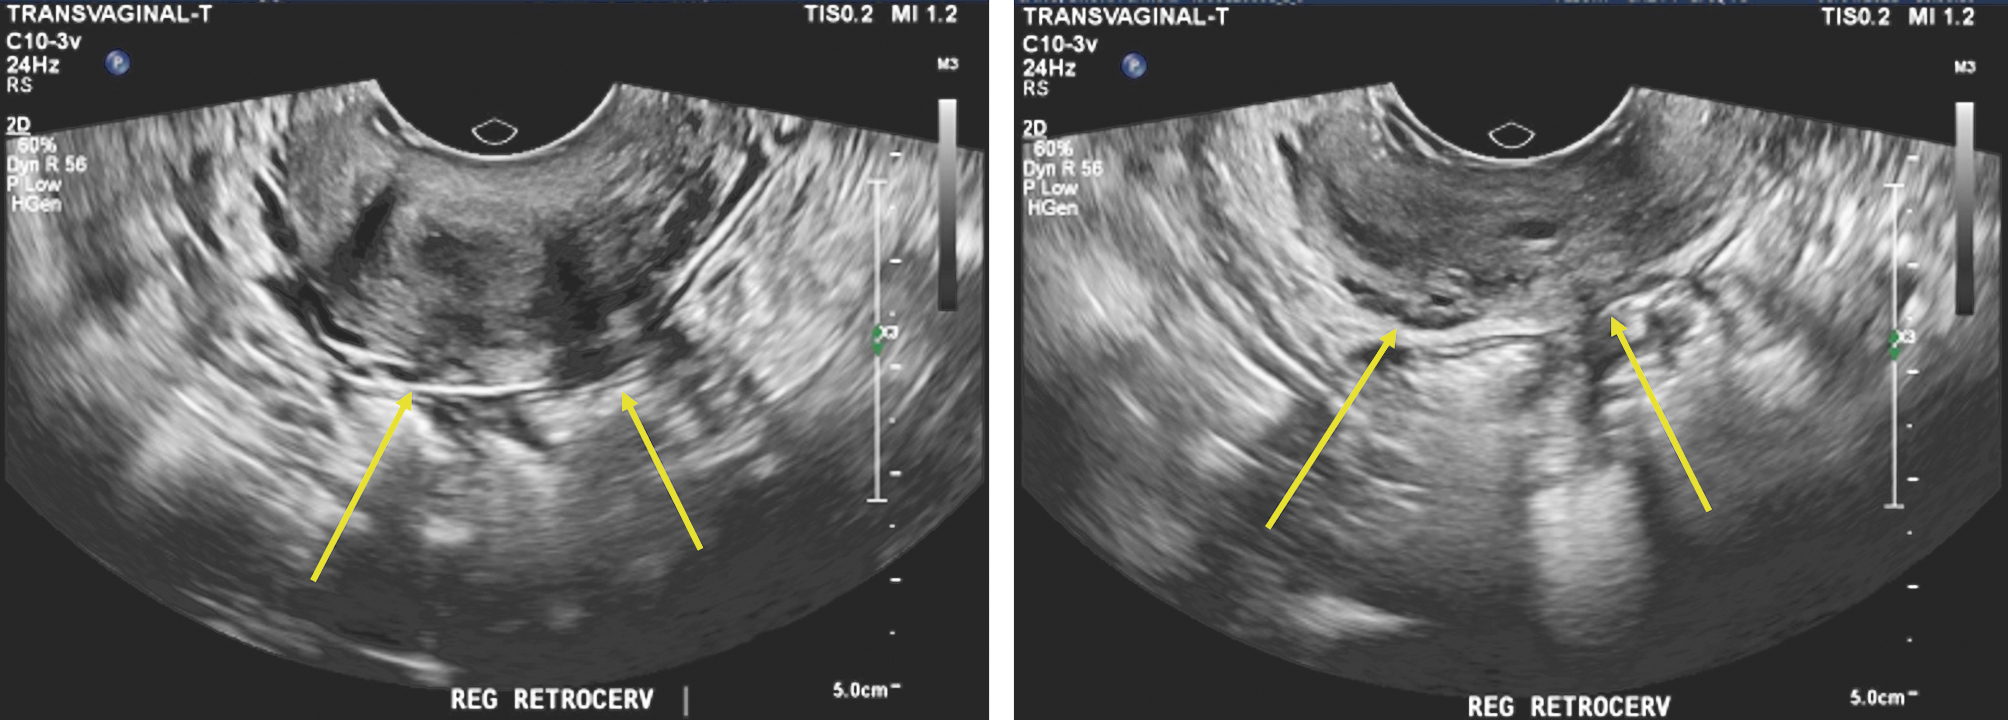

USTV sem preparo intestinal mostra imagem nodular junto ao fórnice posterior medindo 1,3 x 0,7 x 1,0 cm, com espessamento tecidual hipoecogênico, provavelmente em parede do reto alto, com medidas de 2,2 x 1,0 cm

USTV com preparo intestinal confirma lesão com características de endometriose na região do tórus uterino e dos ligamentos uterossacros

USTV com preparo intestinal exibe extensão paravaginal direita no trajeto do plexo hipogástrico inferior direito e invasão das paredes vaginal e do reto, onde há lesão que acomete a camada muscular, com 2,6 x 1,8 x 1,5 cm, a 7,9 cm da borda anal, envolvendo 25% da circunferência da alça.